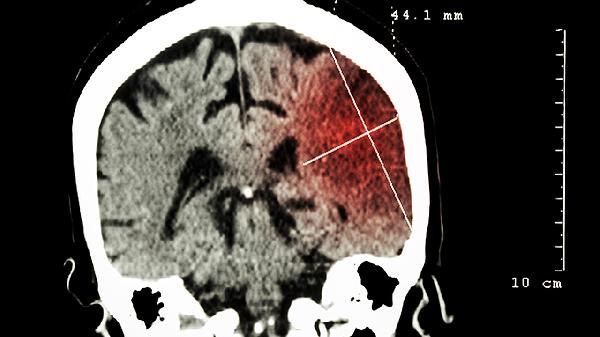

腦部CT一般能檢查出腦瘤,但檢出率與腫瘤大小、位置及類型有關(guān)。腦部CT主要通過X線成像顯示腦組織密度差異,對鈣化、出血及較大腫瘤敏感,但對早期微小腫瘤或低密度病灶可能漏診。

腦部CT對高密度或占位性病變的檢出效果較好,如腦膜瘤、膠質(zhì)瘤等常見腫瘤。這類腫瘤通常因密度高于正常腦組織而在CT圖像中呈現(xiàn)明顯對比,同時可能伴隨周圍水腫或中線結(jié)構(gòu)移位等間接征象。對于直徑超過5毫米的實(shí)質(zhì)性腫瘤或伴有鈣化、出血的病灶,CT診斷準(zhǔn)確率較高,可初步判斷腫瘤性質(zhì)及對周圍組織的壓迫情況。